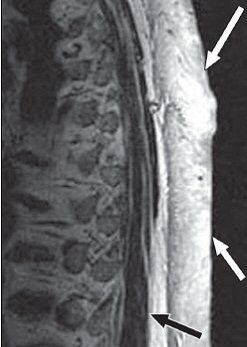

On the T1-weighted MR studies, signal intensity was similar to or mildly higher than that of skeletal muscle. On T2-weighted imaging, lesions were either mildly or markedly hyperintense to muscle. Enhancement was universally intense on contrast-enhanced MR.

| A 65-year-old man with plaque-like diffuse neurofibroma. Above, sagittal T1-weighted MR image (TR/TE, 500/16) shows thick plaque-like diffuse neurofibroma involving skin and subcutaneous tissues of back. Deep aspect (black arrow) of mass is well-defined, and deeper subcutaneous tissues are uninvolved. Small flow voids (white arrows) reflect prominent internal vascularity. Below, sagittal T2-weighted MR image (3,200/104) shows diffuse neurofibroma (white arrows) that is markedly hyperintense in relation to muscle (black arrow). |

![]() |